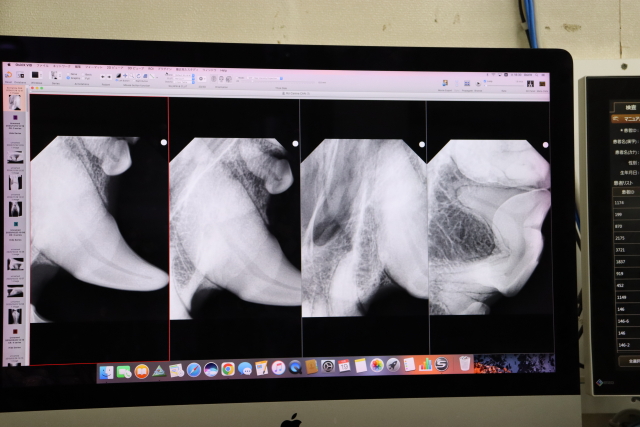

【4】左上の犬歯、奥歯のレントゲン=骨まできていると黒く写るそうですが、

“もに”の歯の骨は黒くなっていないので骨は大丈夫で抜歯の必要はなし!

また骨まできていると鼻水やくしゃみがでるそうですが、“もに”は鼻水もくしゃみありません。